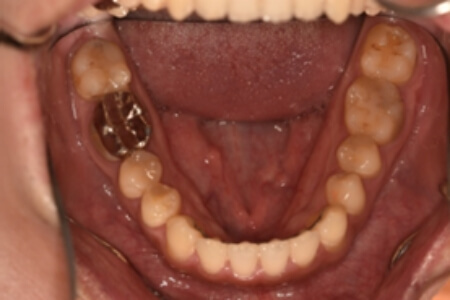

| 治療内容の詳細 | 初診時26歳の男性で、受け口を気にされ来院されました。 検査の結果、下顎前突、上顎前歯部叢生および上顎側切歯反対咬合を伴うアングルⅢ級不正咬合と診断しました。 先ず、前期治療として、リンガルアーチを使用し、上顎中切歯を前方へ移動させ、反対咬合の改善を行いました。 その後、マウスピース型矯正装置(インビザライン)で配列を行いました。 治療期間としては1年8か月でした。 |